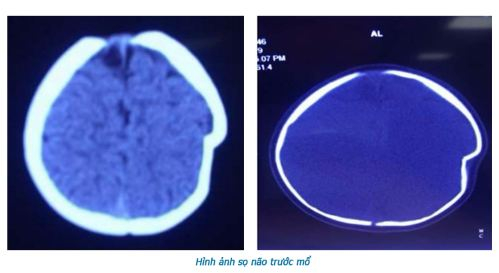

Thông tin từ Khoa Ngoại Thần kinh, Bệnh viện đa khoa tỉnh Phú Thọ, mới đây, các bác sĩ của khoa đãtiếp nhận và tiến hành phẫu thuật để nâng xương lún cho bệnh nhi 8 tháng tuổi bị ngã lún sọ thái dương đỉnh trái.

Tại đây, bé L đã được làm các cận lâm sàng và được chẩn đoán lún sọ thái dương đỉnh trái, vết lún sâu 1cm.

BSCKII, Hà Xuân Tài, Phó Khoa Ngoại Thần kinh, Bệnh viện Đa khoa tỉnh Phú Thọ, trực tiếp phẫu thuật cho bệnh nhi L cho biết: “Lún sọ pingpong thường gặp ở trẻ nhũ nhi dưới 1 tuổi. Nguyên nhân thường do tai biến sinh có thủ thuật, hay trẻ bị ngã khi tập đứng, tập đi và trẻ bị ngã ở độ cao thấp. Vị trí thường gặp hộp sọ là vùng đỉnh. Do ở trẻ nhũ nhi hộp sọ có khả năng tự điều chỉnh tốt nên hiếm khi phải mổ cấp cứu ngay, trừ những trường hợp lún sọ mức độ nhiều, tổn thương rách màng cứng và tổn thương não. Tuy nhiên cha mẹ thường rất lo lắng và yêu cầu được mổ ngay vì liên quan đến thẩm mỹ hộp sọ và sợ ảnh hưởng đến thần kinh của trẻ về sau”.